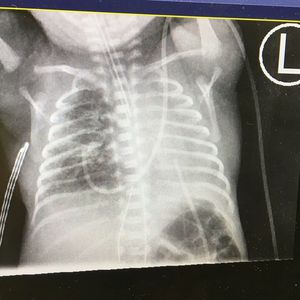

Cxray collapsed left lung

Ex 24w, CA 26 with PIE, RDS, with a right mainstem intubation causing the left lung to collapse ! Pulled the ETT and voila it’s fixed.